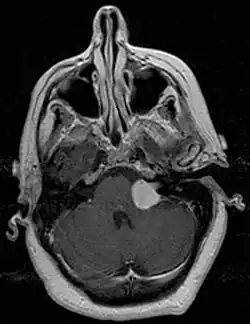

MRI scan is the imaging of choice because it can more accurately differentiate the mass from other tumors such as meningioma, facial nerve schwannoma, epidermoid cyst, arachnoid cyst, aneurysm, and brain metastasis. MRI scan also helps in surgical planning and follow-up of the tumor after surgery.[19] VS is usually isointense on T1 weighted images, hyperintense on T2 weighted images, and enhances after given gadolinium contrast.[20]